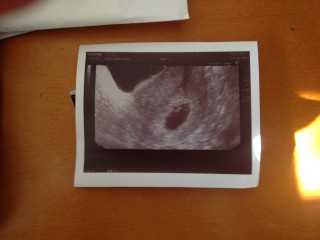

少量の出血があり不安で病院へ。。 心拍確認出来ました!! 初めての妊娠でまだまだ不安ですが。。 一安心